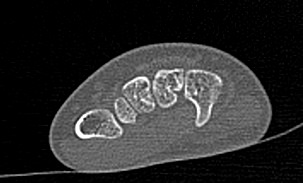

Кисти рук имеют сложное анатомическое строение. Кисть состоит из трех отделов:

- запястье (образовано 8-ю костями), которое участвует в формировании лучезапястного сустава;

- пясть (состоит из 5 трубчатых пястных костей);

- пальцы рук (состоят из 2 или 3 мелких трубчатых костей, соединенных межфаланговыми суставами).

Метод мультиспиральной КТ основан на использовании ионизирующего излучения, которое используется для послойного сканирования внутренних структур организма. Благодаря тончайшим срезам и последующей цифровой обработке полученных данных получаются послойные снимки и 3D-изображения кистей рук в мельчайших подробностях.

Наиболее распространенной причиной диагностической процедуры является травматическое повреждение. Переломы мелких костей на рентгенограмме зачастую могут визуализироваться неотчетливо за счет наложения костных структур друг на друга, а компьютерная томография позволяет различать все кости отдельно и является «золотым стандартом» для исключения повреждения костей.

Компьютерная томография лучше всего подходит для обследования костных структур, так как кости в большей степени поглощают рентгеновские лучи и поэтому хорошо видны на снимках. Для того, чтобы улучшить визуализацию мягких тканей, дополнительно проводится контрастное усиление. Обычно это применяется при подозрении на развитие опухолевых образований.